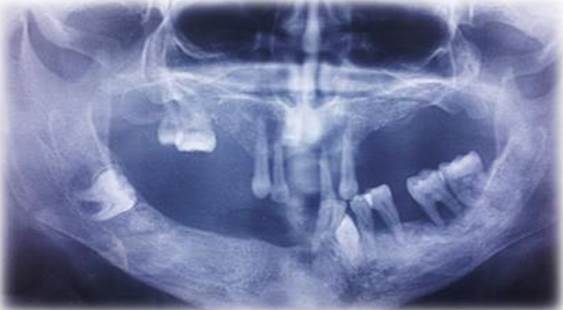

A partir de la presentación del caso, los profesionales de la salud ordenaron ortopantomografía de los maxilares, en la cual se evidenciaron múltiples órganos dentarios retenidos a nivel de línea media del maxilar superior, región premolar inferior izquierda, tercer molar inferior derecho incluido (Imagen 3). Además, se observó amplia pérdida ósea vertical y horizontal.

Se evidencia prótesis parcial removible desadaptada, con presencia de órgano dentario adosado a esta hiperplasia fibrosa inflamatoria en zona anterior del reborde marginal anterior